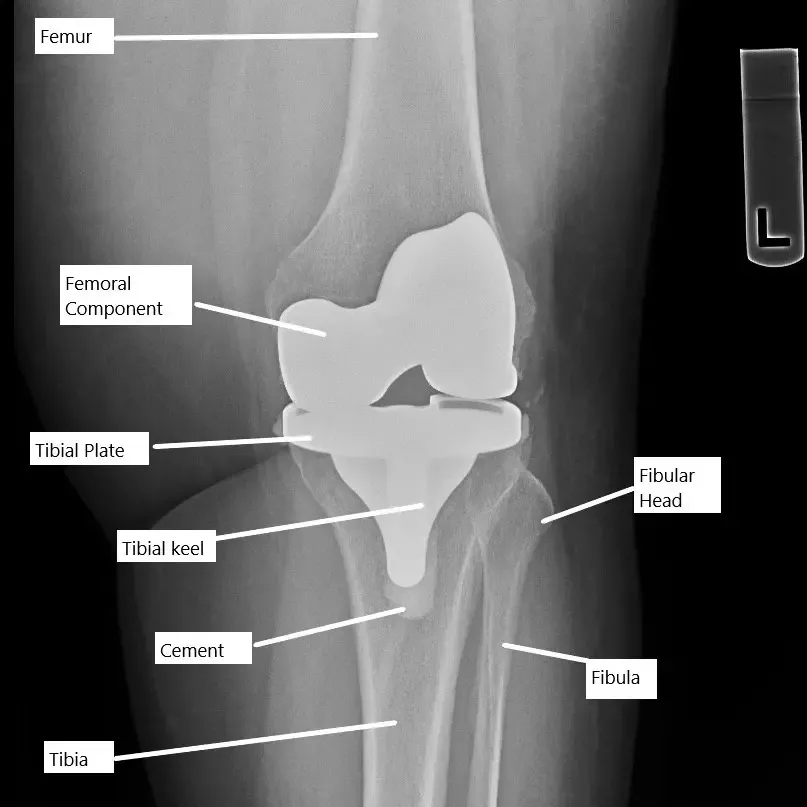

Radiografía de una prótesis total de rodilla.

La articulación de la rodilla es una articulación de bisagra que permite doblar (flexión) y enderezar (extensión) la pierna. La cirugía de prótesis de rodilla consiste en sustituir las superficies dañadas de la rodilla por una prótesis de metal y plástico para recuperar la movilidad. Normalmente, la rodilla puede flexionarse desde 0 grados (totalmente recta) hasta unos 135 grados (totalmente doblada). Tras la operación, es esencial una amplitud de movimiento (ROM) adecuada para las actividades cotidianas, como andar, sentarse o subir escaleras.